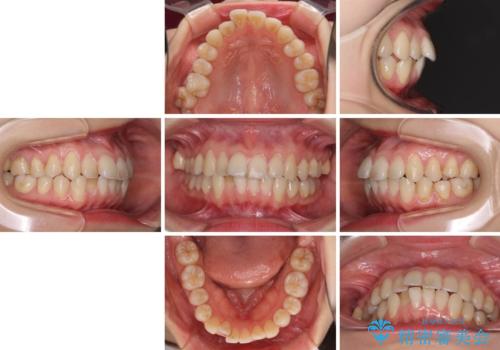

- 上下前歯のデコボコを気にして来院された患者様です。

インビザラインによる上下歯列の側方拡大と後方移動、IPR(歯と歯の間を削る)にるスペースの獲得により歯列を整えることとしました。

1日22時間の装着時間をしっかり守ってくださったので、予定していた1年よりも早く治療を終えることができました。

インビザライン矯正特有の奥歯がしっかりと咬合しない感覚も改善され、大変満足していただきました。